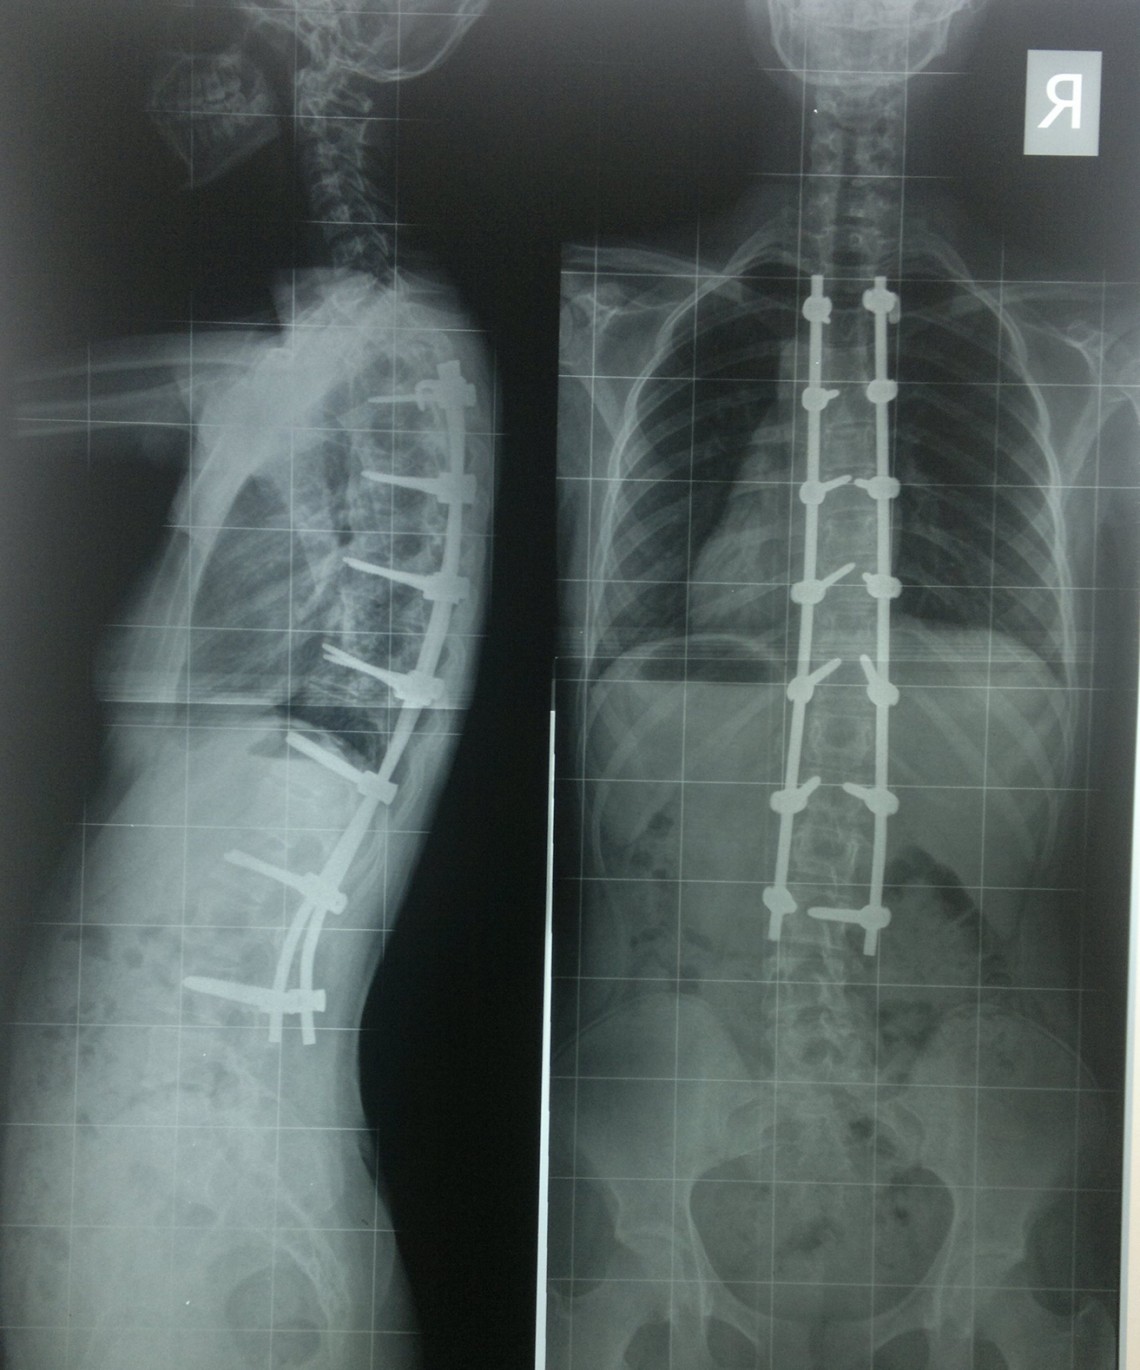

Farklı tipte skolyozu olan hastaların ameliyat öncesi ve sonrası fotoları: